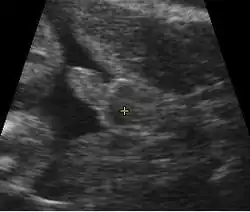

![]() Obstetric sonogram of a fetus at 16 weeks. The bright white circle center-right is the head, which faces to the left. Features include the forehead at 10 o'clock, the left ear toward the center at 7 o'clock and the right hand covering the eyes at 9:00. | |